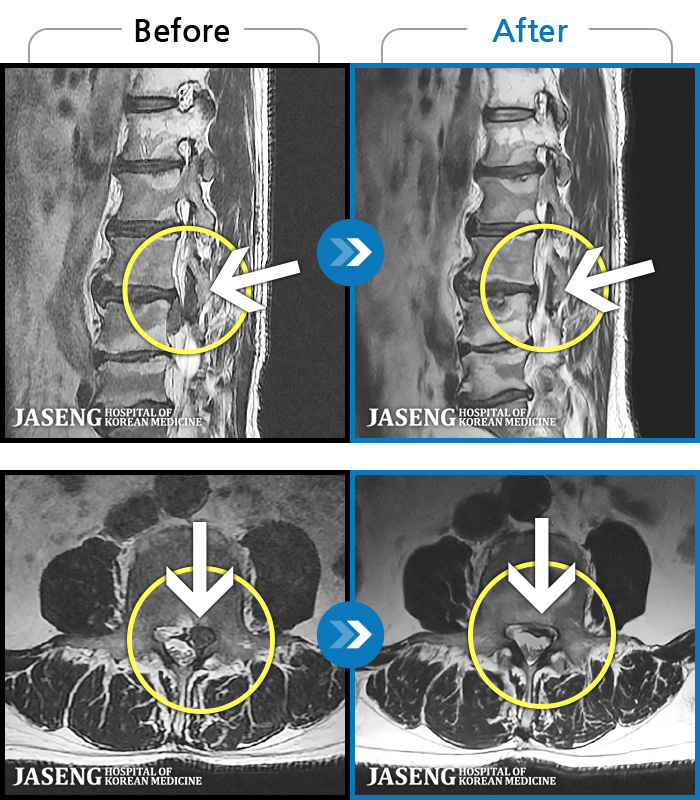

MRI ġ

1,304 MRI ũ ʸ Ȯϼ.